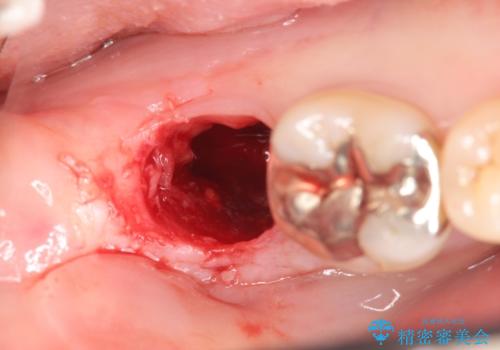

- 右下奥歯がグラグラし、噛めないことの改善を希望され来院されました。

X線写真より根尖付近までの骨吸収を認めます。

抜歯を余儀なくされる状況ですが、将来的にインプラントによる咬合機能回復を希望されたので抜歯と同時に骨補填剤を填入し骨の造成をしたのちのインプラント治療を計画します。

歯を失い、将来的にインプラントを埋入し咬合機能を回復していく場合、十分な骨量の確保は重要です。

今回抜歯後、骨が十分に確保できないとの判断から抜歯と同時に骨補填剤の填入を行いました。